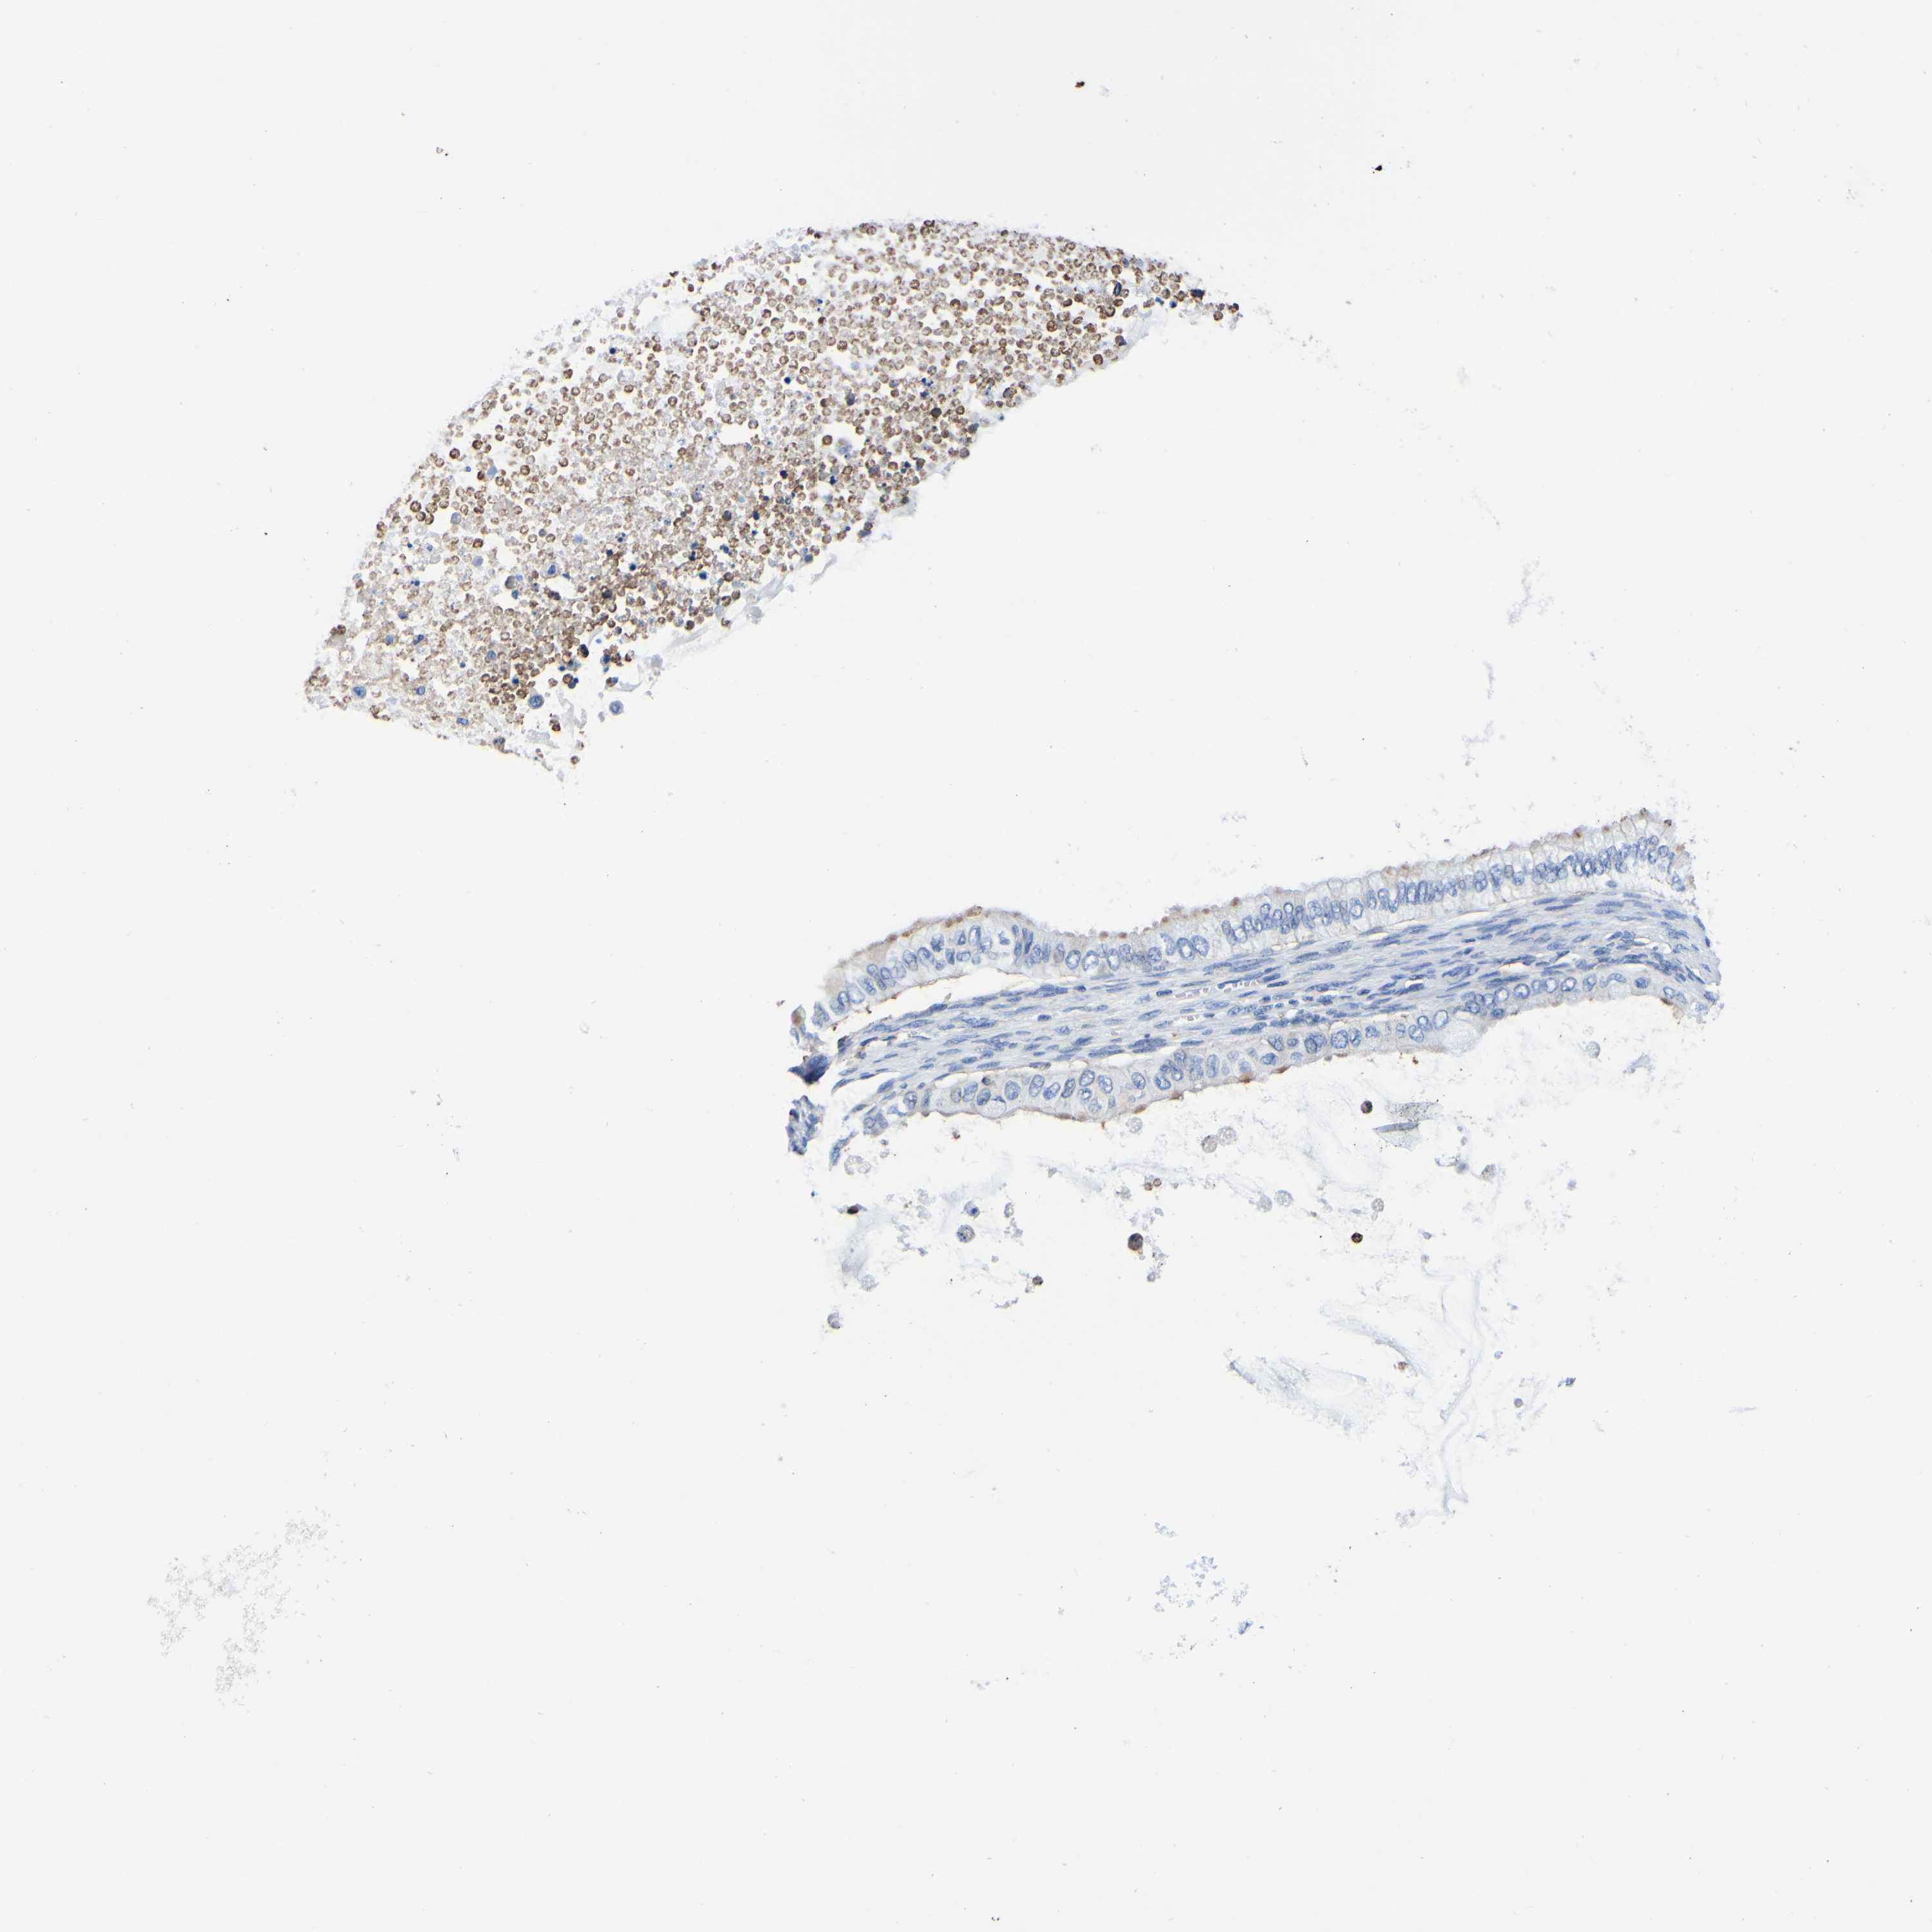

OVARIAN CANCER - Protein expressioni

A mouse-over function shows sample information and annotation data. Click on an image to view it in a full screen mode. Samples can be filtered based on level of antibody staining by selecting one or several of the following categories: high, medium, low and not detected. The assay and annotation is described here.

Note that samples used for immunohistochemistry by the Human Protein Atlas do not correspond to samples in the TCGA dataset.

Antibody stainingi

Antibody staining in the annotated cell types in the current human tissue is reported as not detected, low, medium, or high, based on conventional immunohistochemistry profiling in selected tissues. This score is based on the combination of the staining intensity and fraction of stained cells.

Each image is clickable and will lead to virtual microscopy that enables deeper exploration of all samples and also displays staining intensity scores, fraction scores and subcellular localization as well as patient and tissue information for each sample.

Antibody HPA012375

Staining

High

Medium

Low

Not detected

Intensity

Strong

Moderate

Weak

Negative

Quantity

>75%

75%-25%

<25%

None

Location

Nuclear

Cytoplasmic/membranous

Cytoplasmic/membranous,nuclear

Cystadenocarcinoma, serous, NOS

Carcinoma, endometroid

Cystadenocarcinoma, mucinous, NOS

Carcinoma, NOS